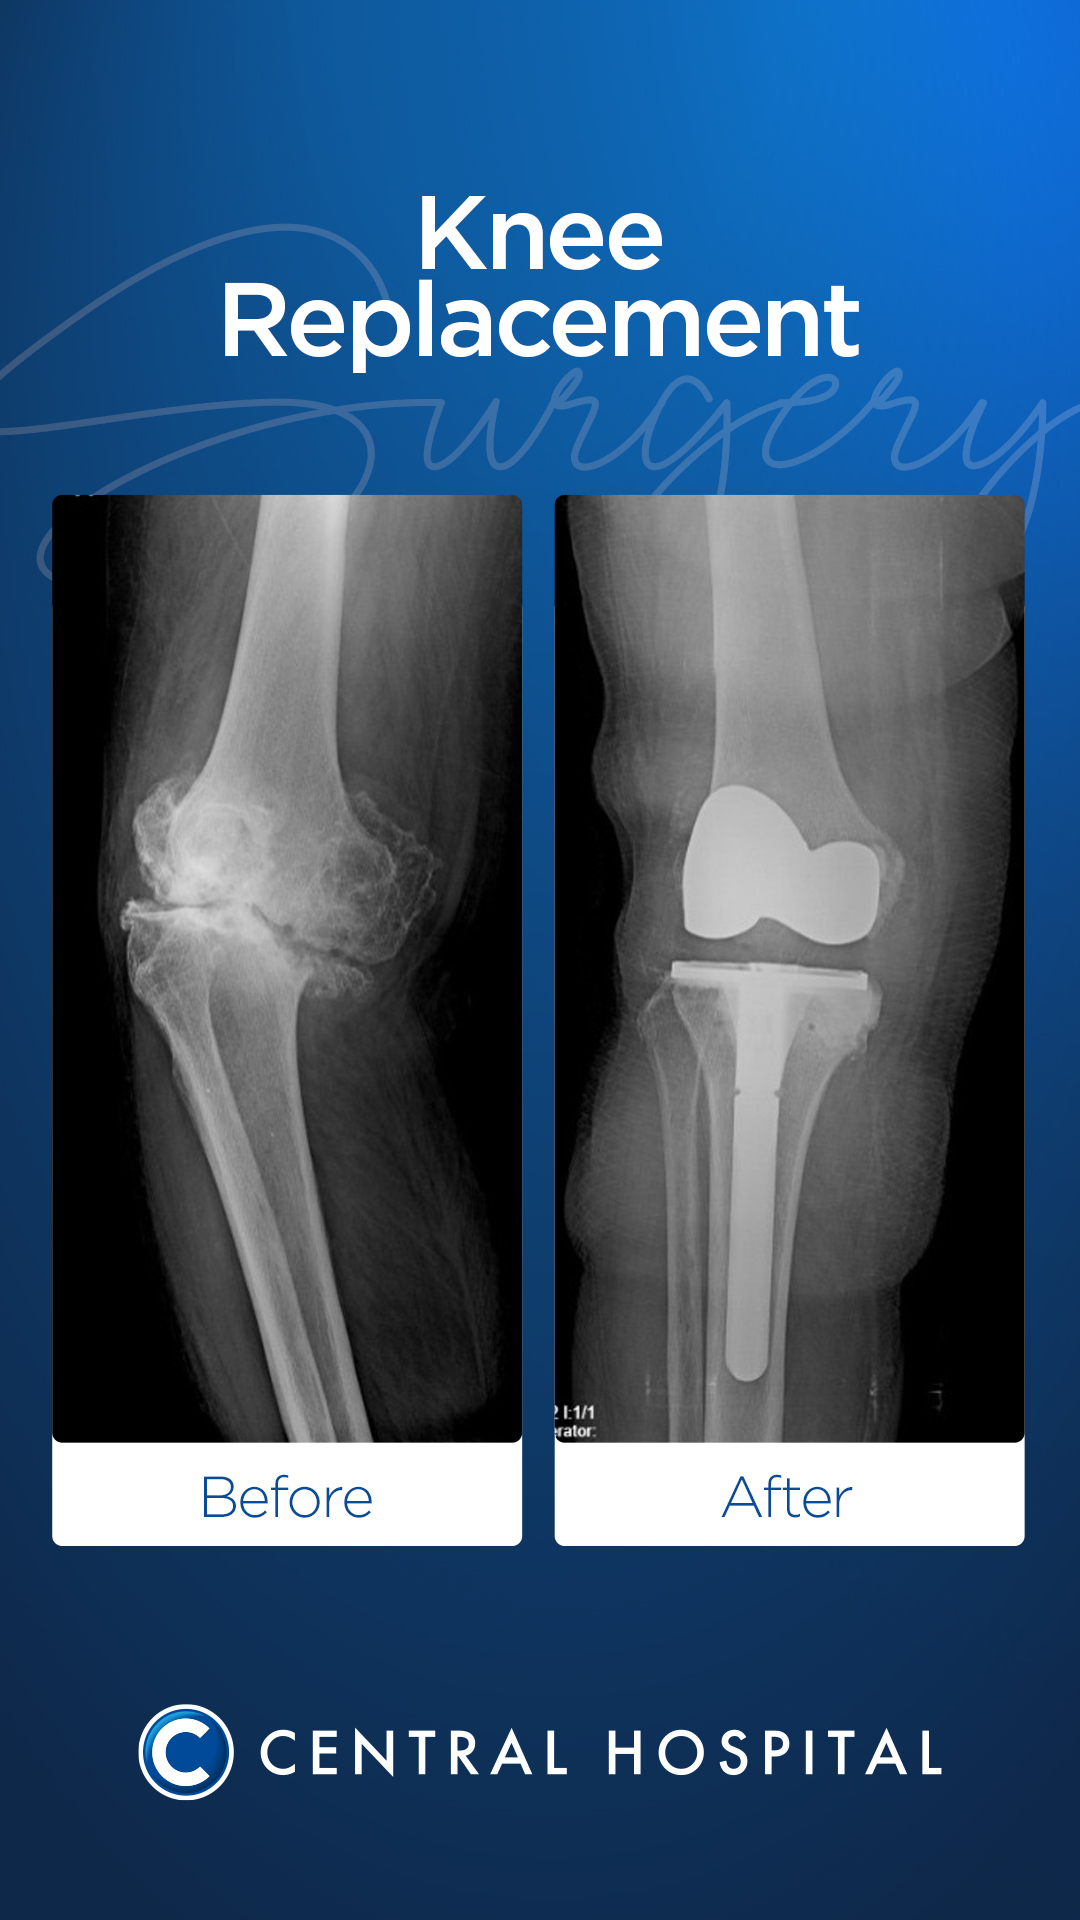

Cirugía de prótesis de rodilla

Durante la operación, las superficies articulares desgastadas y dañadas se limpian cuidadosamente, dejando en su lugar un inserto artificial (prótesis) hecho de metal o aleaciones plásticas especiales. Esta planificación quirúrgica se realiza de forma individual según la edad, el nivel de actividad y la estructura ósea del paciente.